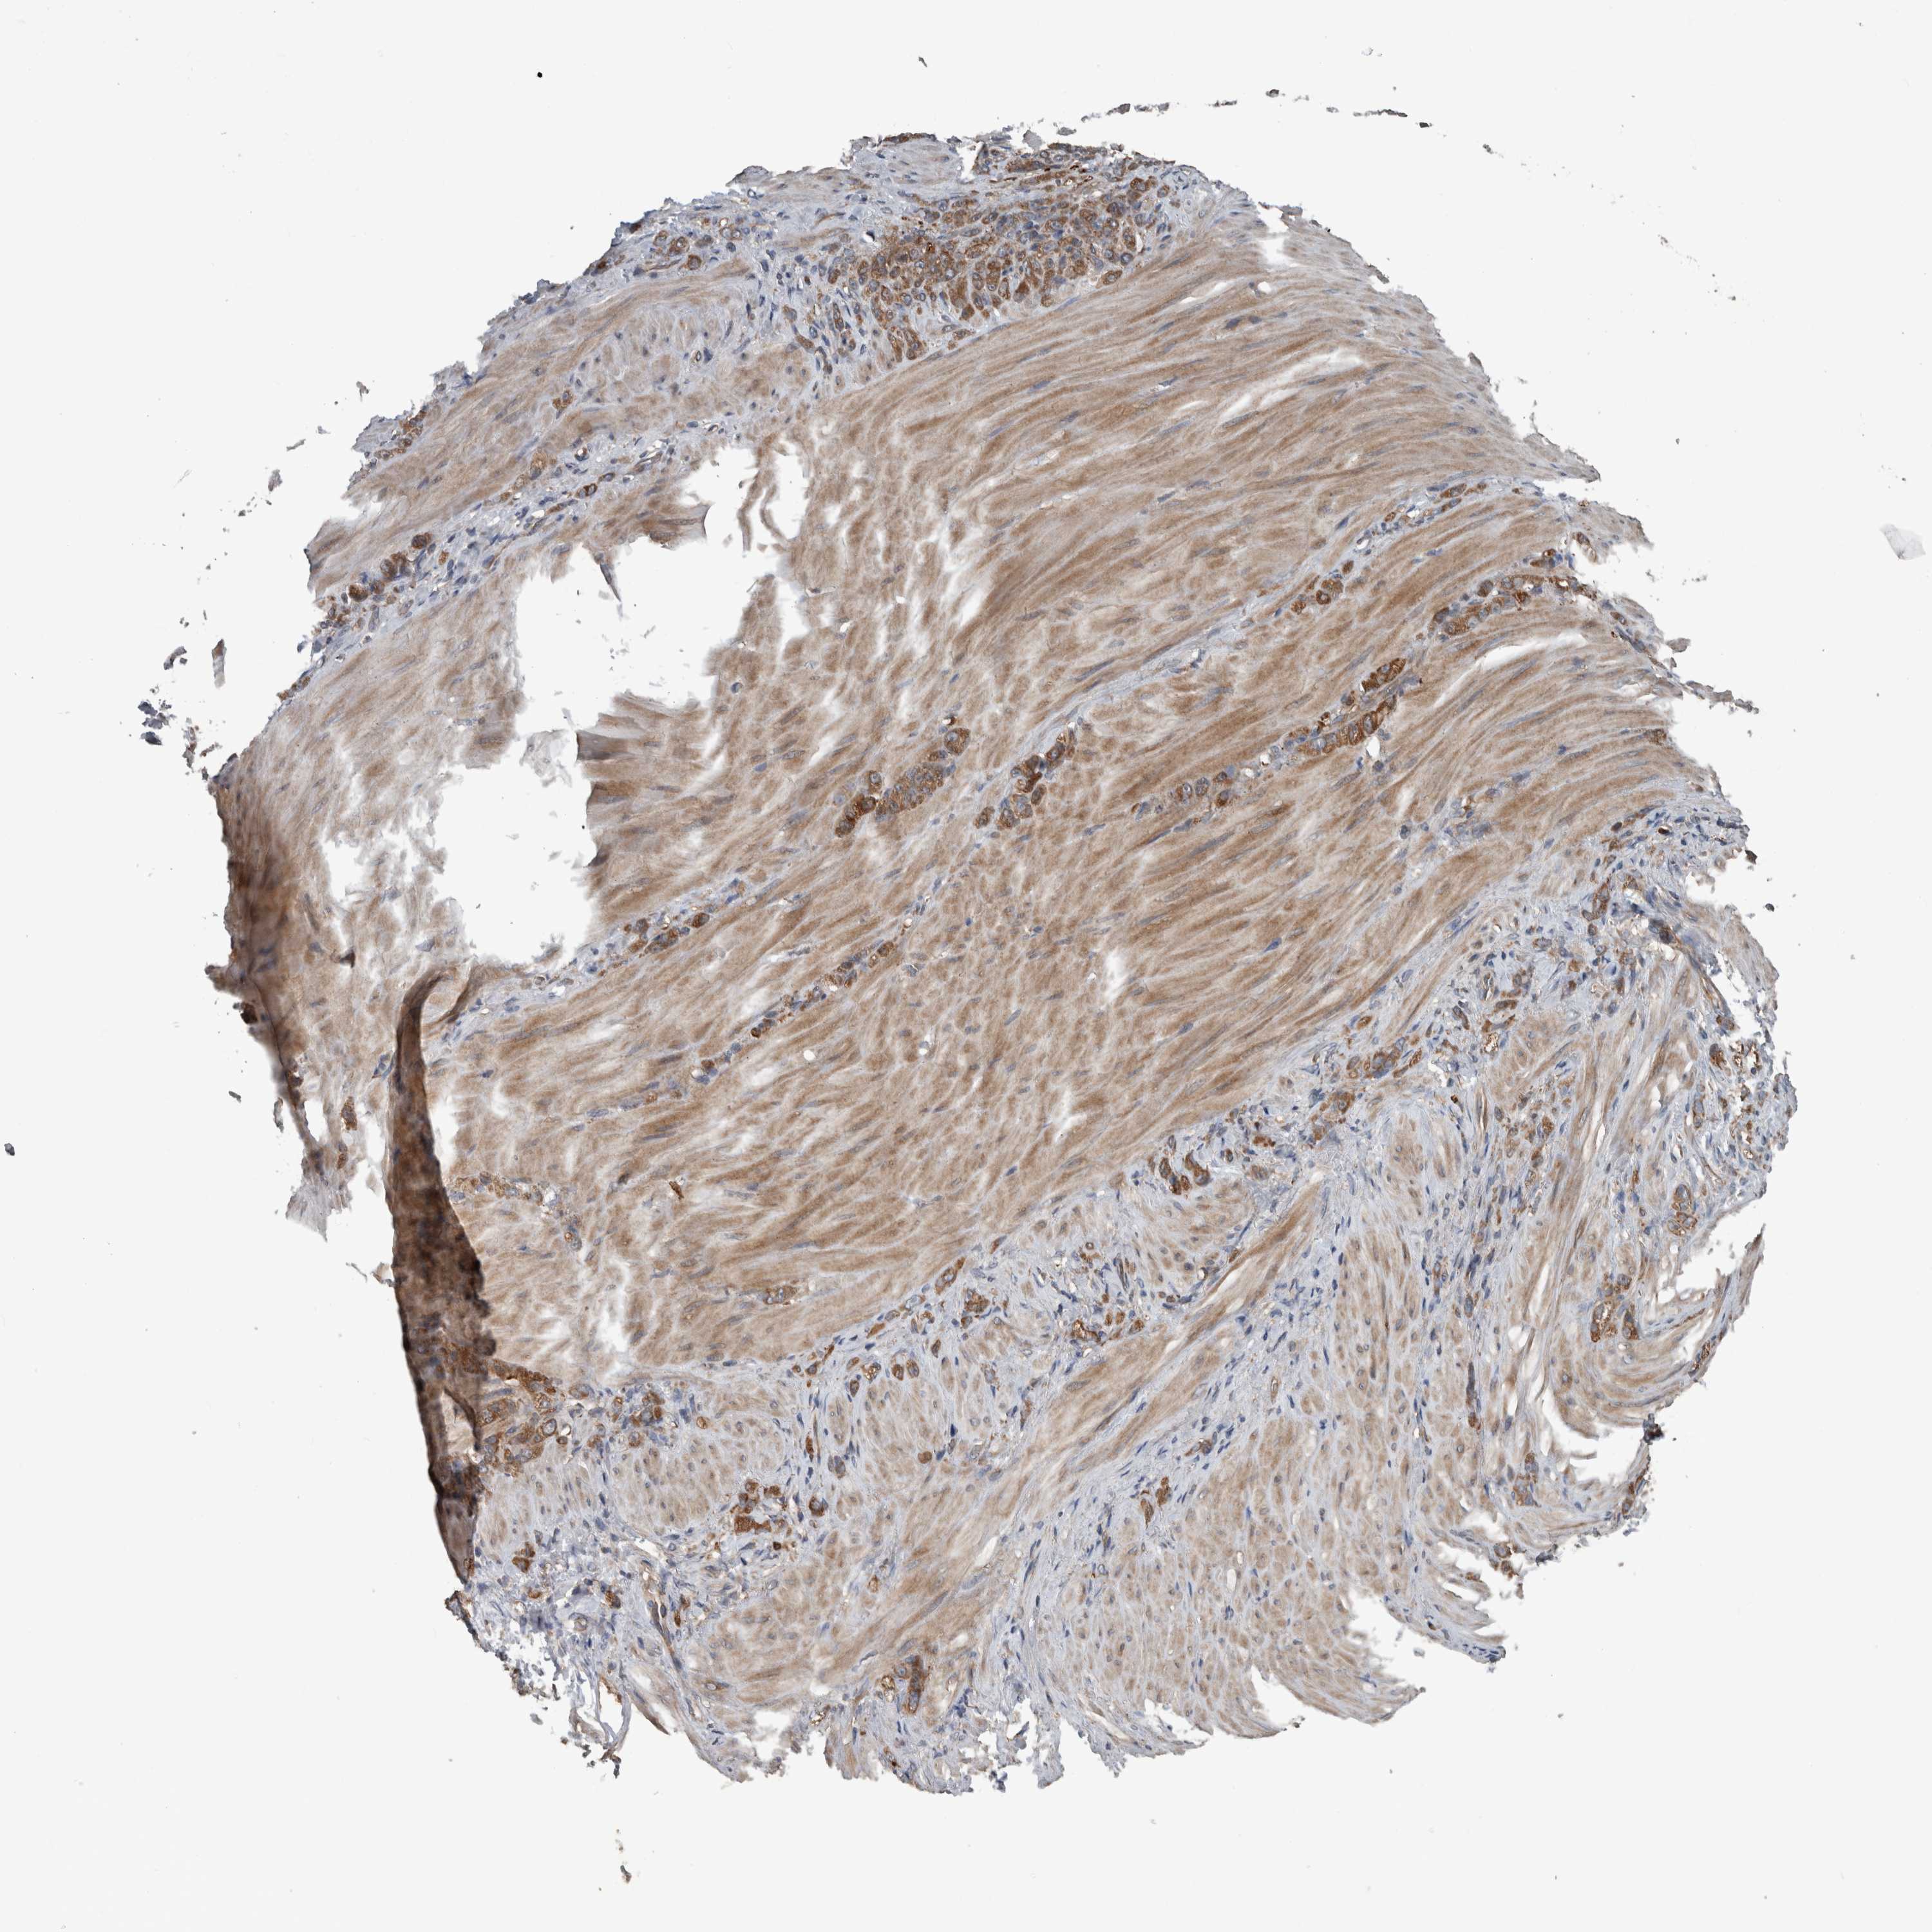

STOMACH CANCER - Protein expressioni

A mouse-over function shows sample information and annotation data. Click on an image to view it in a full screen mode. Samples can be filtered based on level of antibody staining by selecting one or several of the following categories: high, medium, low and not detected. The assay and annotation is described here.

Note that samples used for immunohistochemistry by the Human Protein Atlas do not correspond to samples in the TCGA dataset.

Antibody stainingi

Antibody staining in the annotated cell types in the current human tissue is reported as not detected, low, medium, or high, based on conventional immunohistochemistry profiling in selected tissues. This score is based on the combination of the staining intensity and fraction of stained cells.

Each image is clickable and will lead to virtual microscopy that enables deeper exploration of all samples and also displays staining intensity scores, fraction scores and subcellular localization as well as patient and tissue information for each sample.

Antibody HPA001620

Antibody HPA024184

Staining

High

Medium

Low

Not detected

Intensity

Strong

Moderate

Weak

Negative

Quantity

>75%

75%-25%

<25%

None

Location

Nuclear

Cytoplasmic/membranous

Cytoplasmic/membranous,nuclear

Adenocarcinoma, NOS